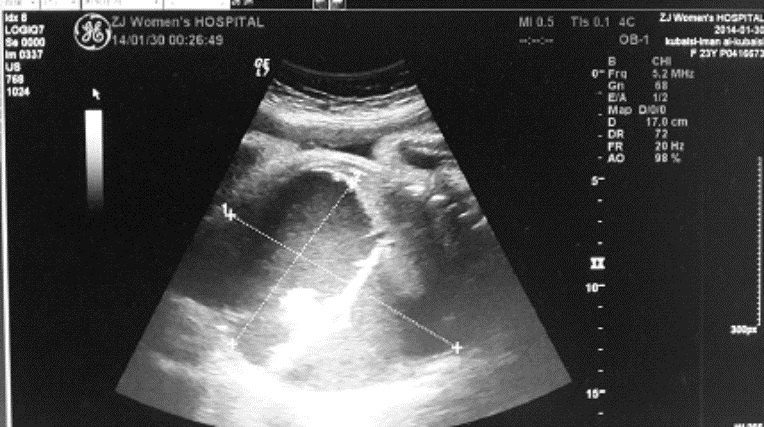

停经37+2周B超示:胎儿腹腔内12.2 cm×9.2 cm×7.2 cm液性暗区,内见分隔样回声,透声差(图 1),同日阴道分娩一男婴,Apgar评分8~9分/1~5 min,体质量2 750 g。新生儿查体:腹胀明显,腹部X线结果:腹部膨隆,两侧膈下无游离气体影,腹腔内中下腹部见不规则团片状及点状稍高密度及高密度影,最大为1.6 cm×1.2 cm,腹内显示少许肠管内有气体,未见明显气-液平面,诊断结果:腹腔囊肿,畸胎瘤?(图 2)。初步诊断:先天性腹腔囊肿,需手术治疗转入浙江大学医学院附属儿童医院。

图 1 孕妇产前B超结果